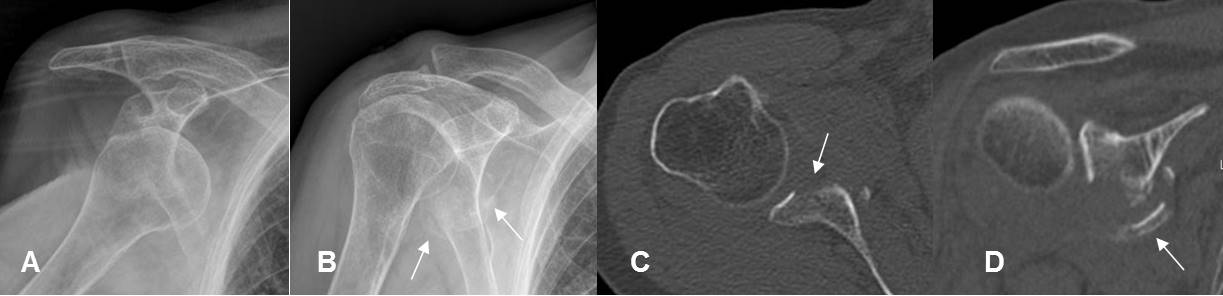

Fig 172. Lesión de Bankart óseo.

A: Rx AP. Luxación anterior del hombro.

B: Rx AP. Después de la reducción, se aprecian fragmentos óseos por debajo de la glenoides.

C: TAC axial. Fractura del borde anterior de la glenoides, por Bankart óseo.

D: TAC reconstrucción coronal. Fractura de la glenoides inferior, con fragmentos desplazados.